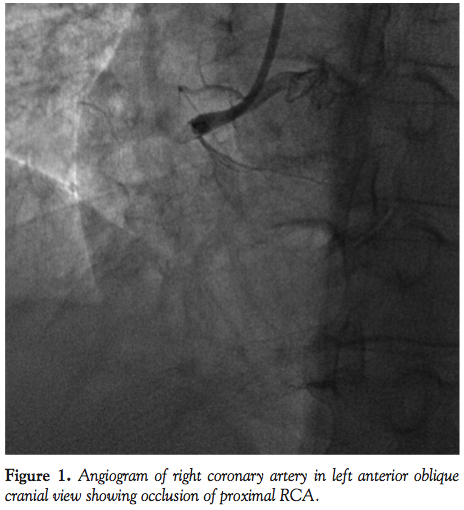

mg), and glycoprotein IIb/IIIa was started. Coronary angiography showed a normal left coronary system and proximal thrombotic occlusion of dominant right coronary artery (RCA) (Figure 1). RCA was engaged with 7 Fr Judkins right guide catheter (Medtronic Vascular) and the lesion was crossed with a stabilizer plus wire (Cordis Corporation). For thrombosuction, a 6 Fr Export catheter (Medtronic) was passed into the RCA. However, repeated attempts failed to restore any flow in the artery. In view of the deteriorating condition of the patient and no response to these pharmacologic and mechanical approaches, guide catheter suction was planned.